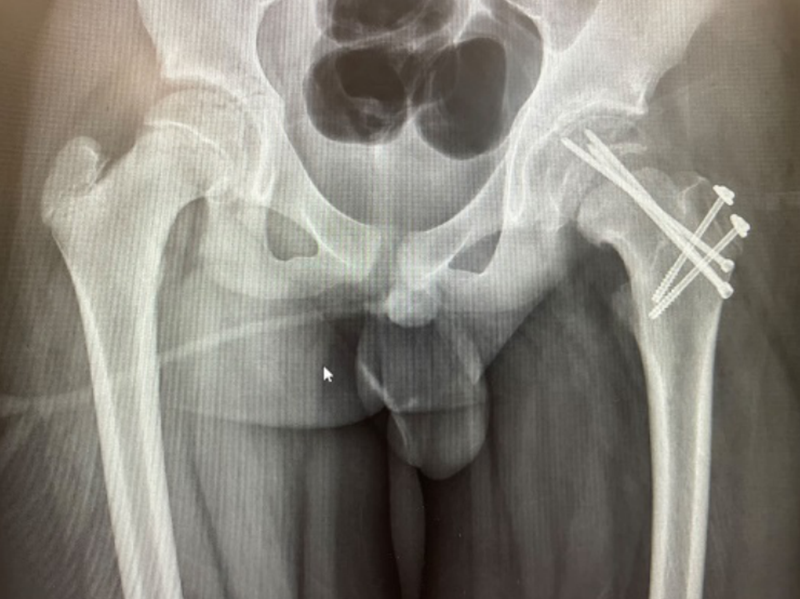

经过检查,小明被诊断为“慢性左股骨头骨骺滑脱(重度)”。因为小明受伤已有一年之久,滑脱的骨骺已经畸形愈合,因此手术不仅要“打断骨头”,复位固定的同时还要尽可能保护患者的股骨头,尽量避免股骨头坏死的发生。经过周密的术前准备,创伤骨科团队制定了详细的手术方案,采用改良Dunn手术技术解剖复位滑脱骨骺,最终顺利完成手术。

住院期间,医生团队早晚查房,密切观察病情变化;护理团队认真负责,悉心呵护。全科医护人员以和蔼可亲、热情周到的服务,不辞辛劳、不怕麻烦的精神,赢得了患者及其家属的赞誉。看着患者术后的X片,患者家属激动地说:“感谢柳人医创伤骨科团队,你们的技术一流,医德医风也很好,把我们这么难治的病都治好了。”

术后X片影像